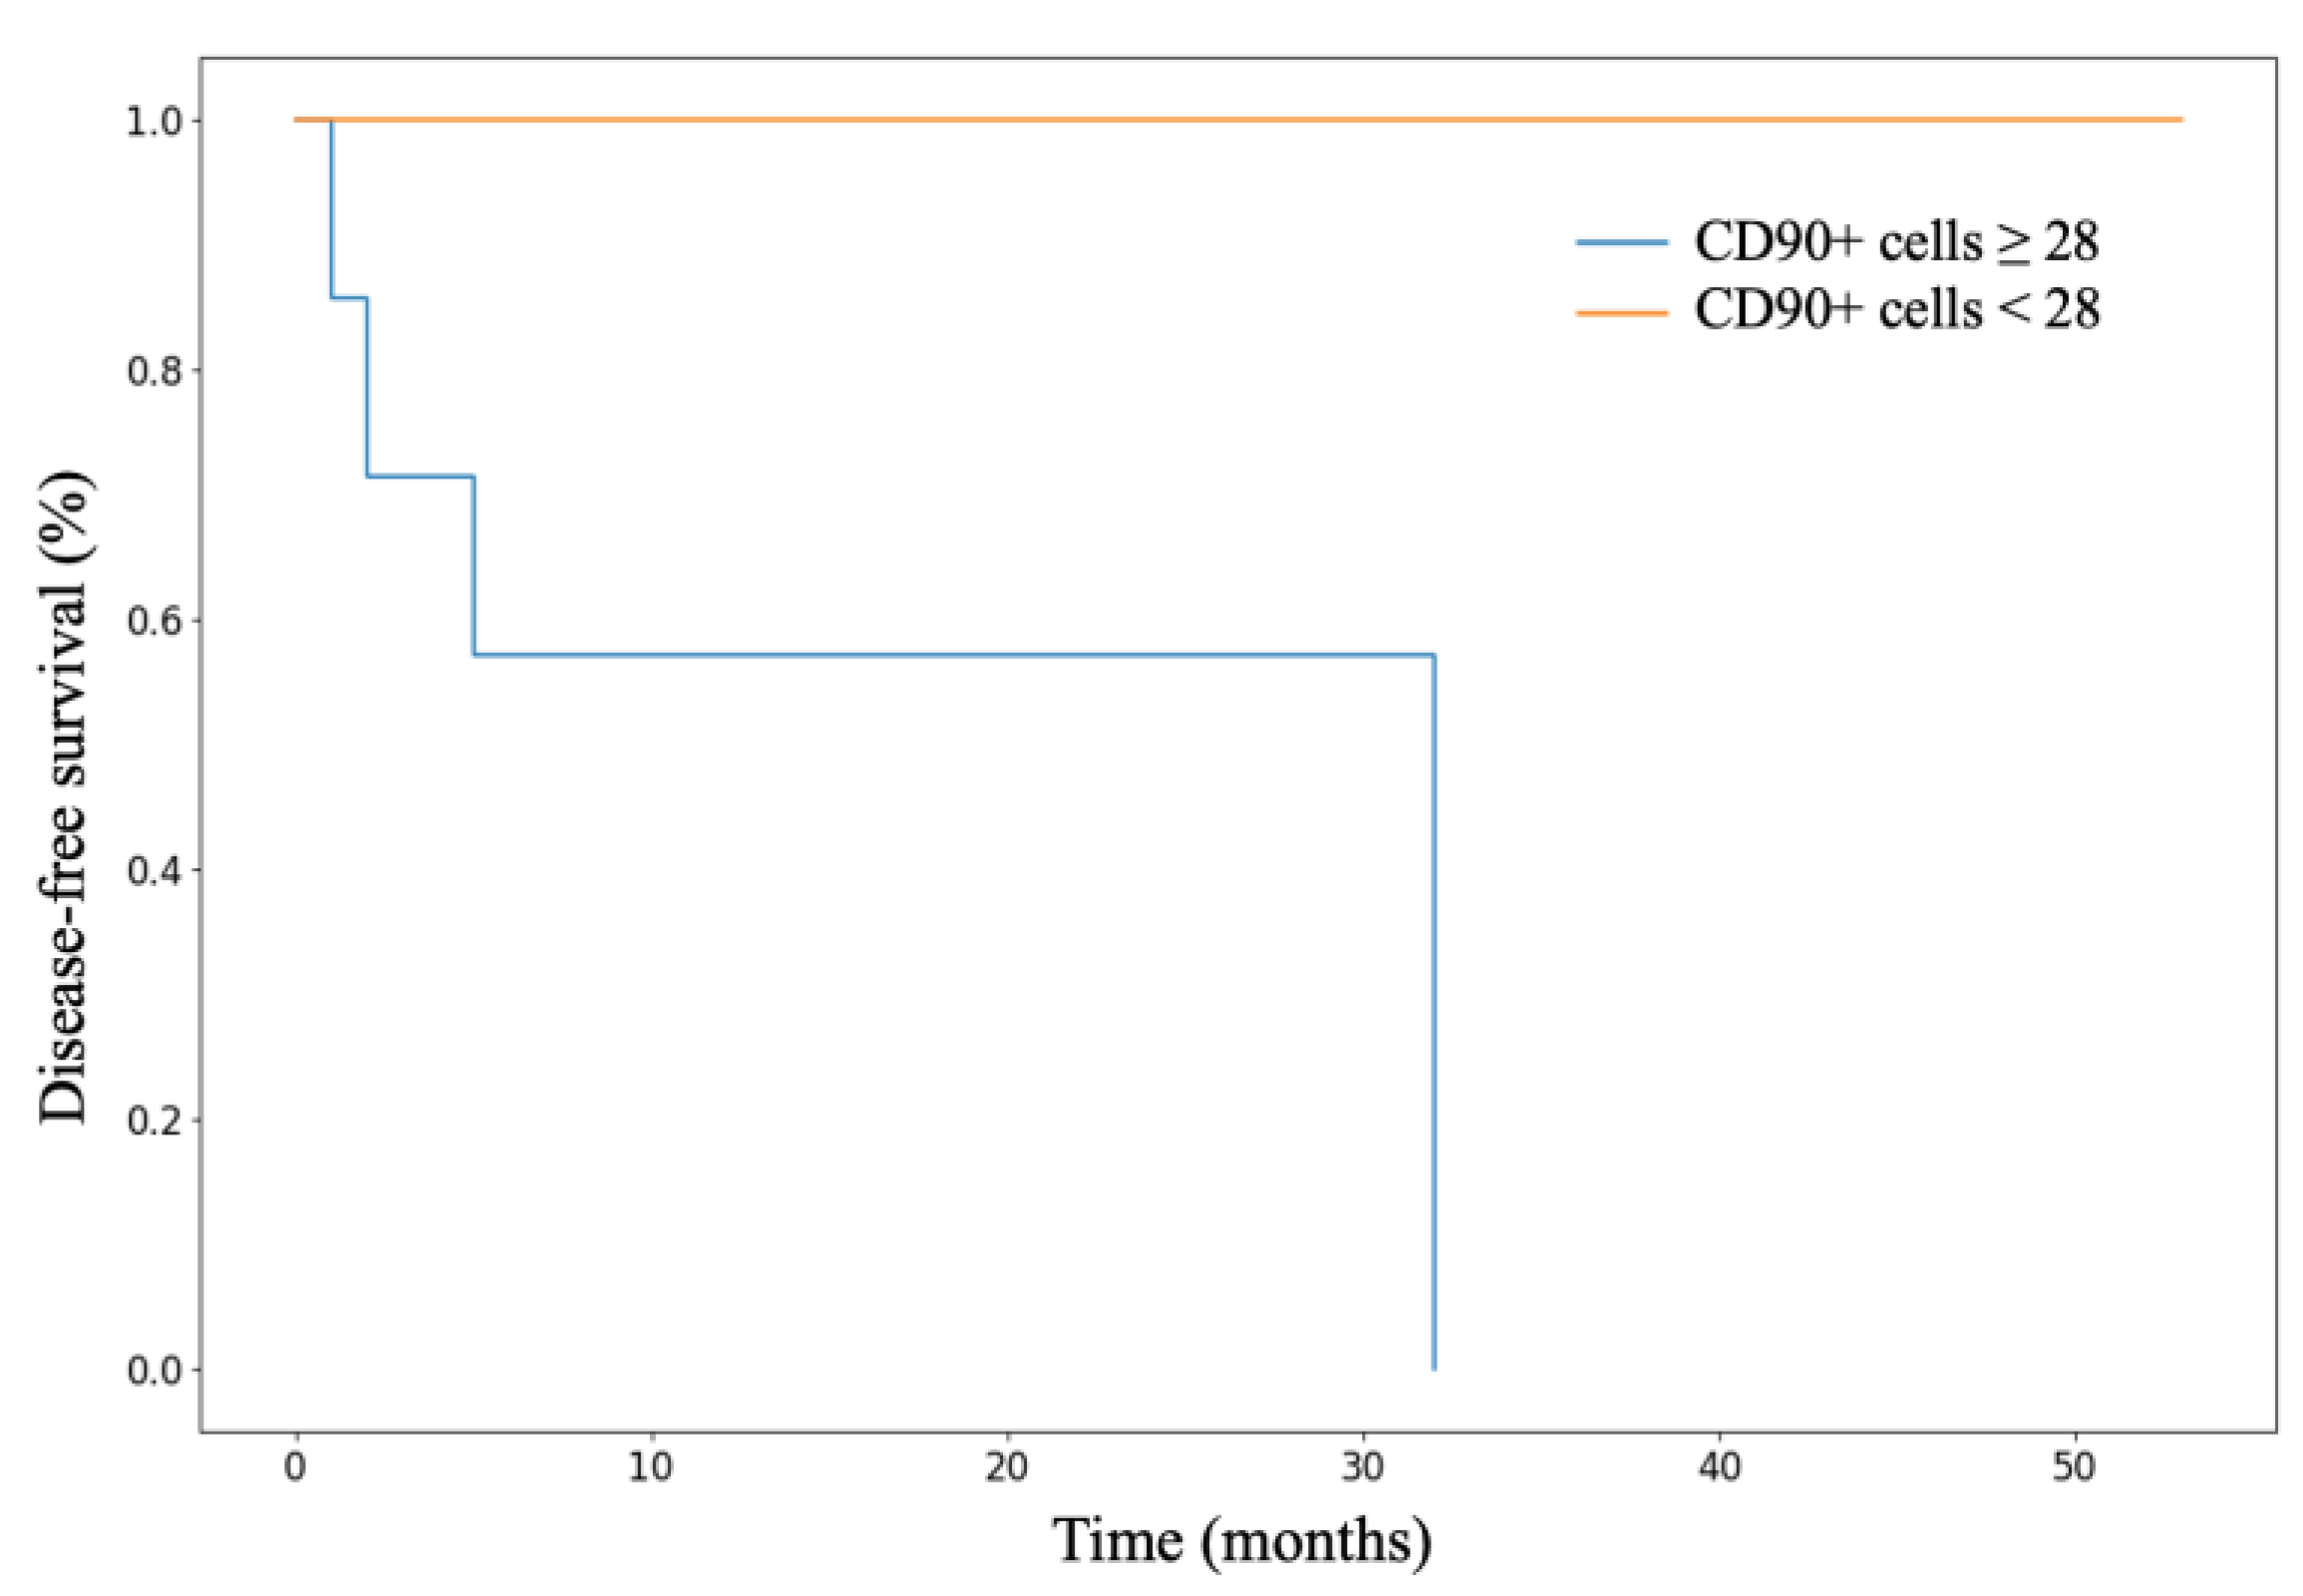

3.3. Analysis of Patient Survival Depending on the Expression of Stem Markers